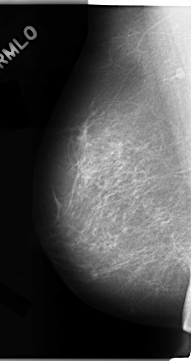

C_0047_1.RIGHT_MLO

RIGHT_MLO LINES 4688 PIXELS_PER_LINE 2488 BITS_PER_PIXEL 12 RESOLUTION 50 NON_OVERLAY